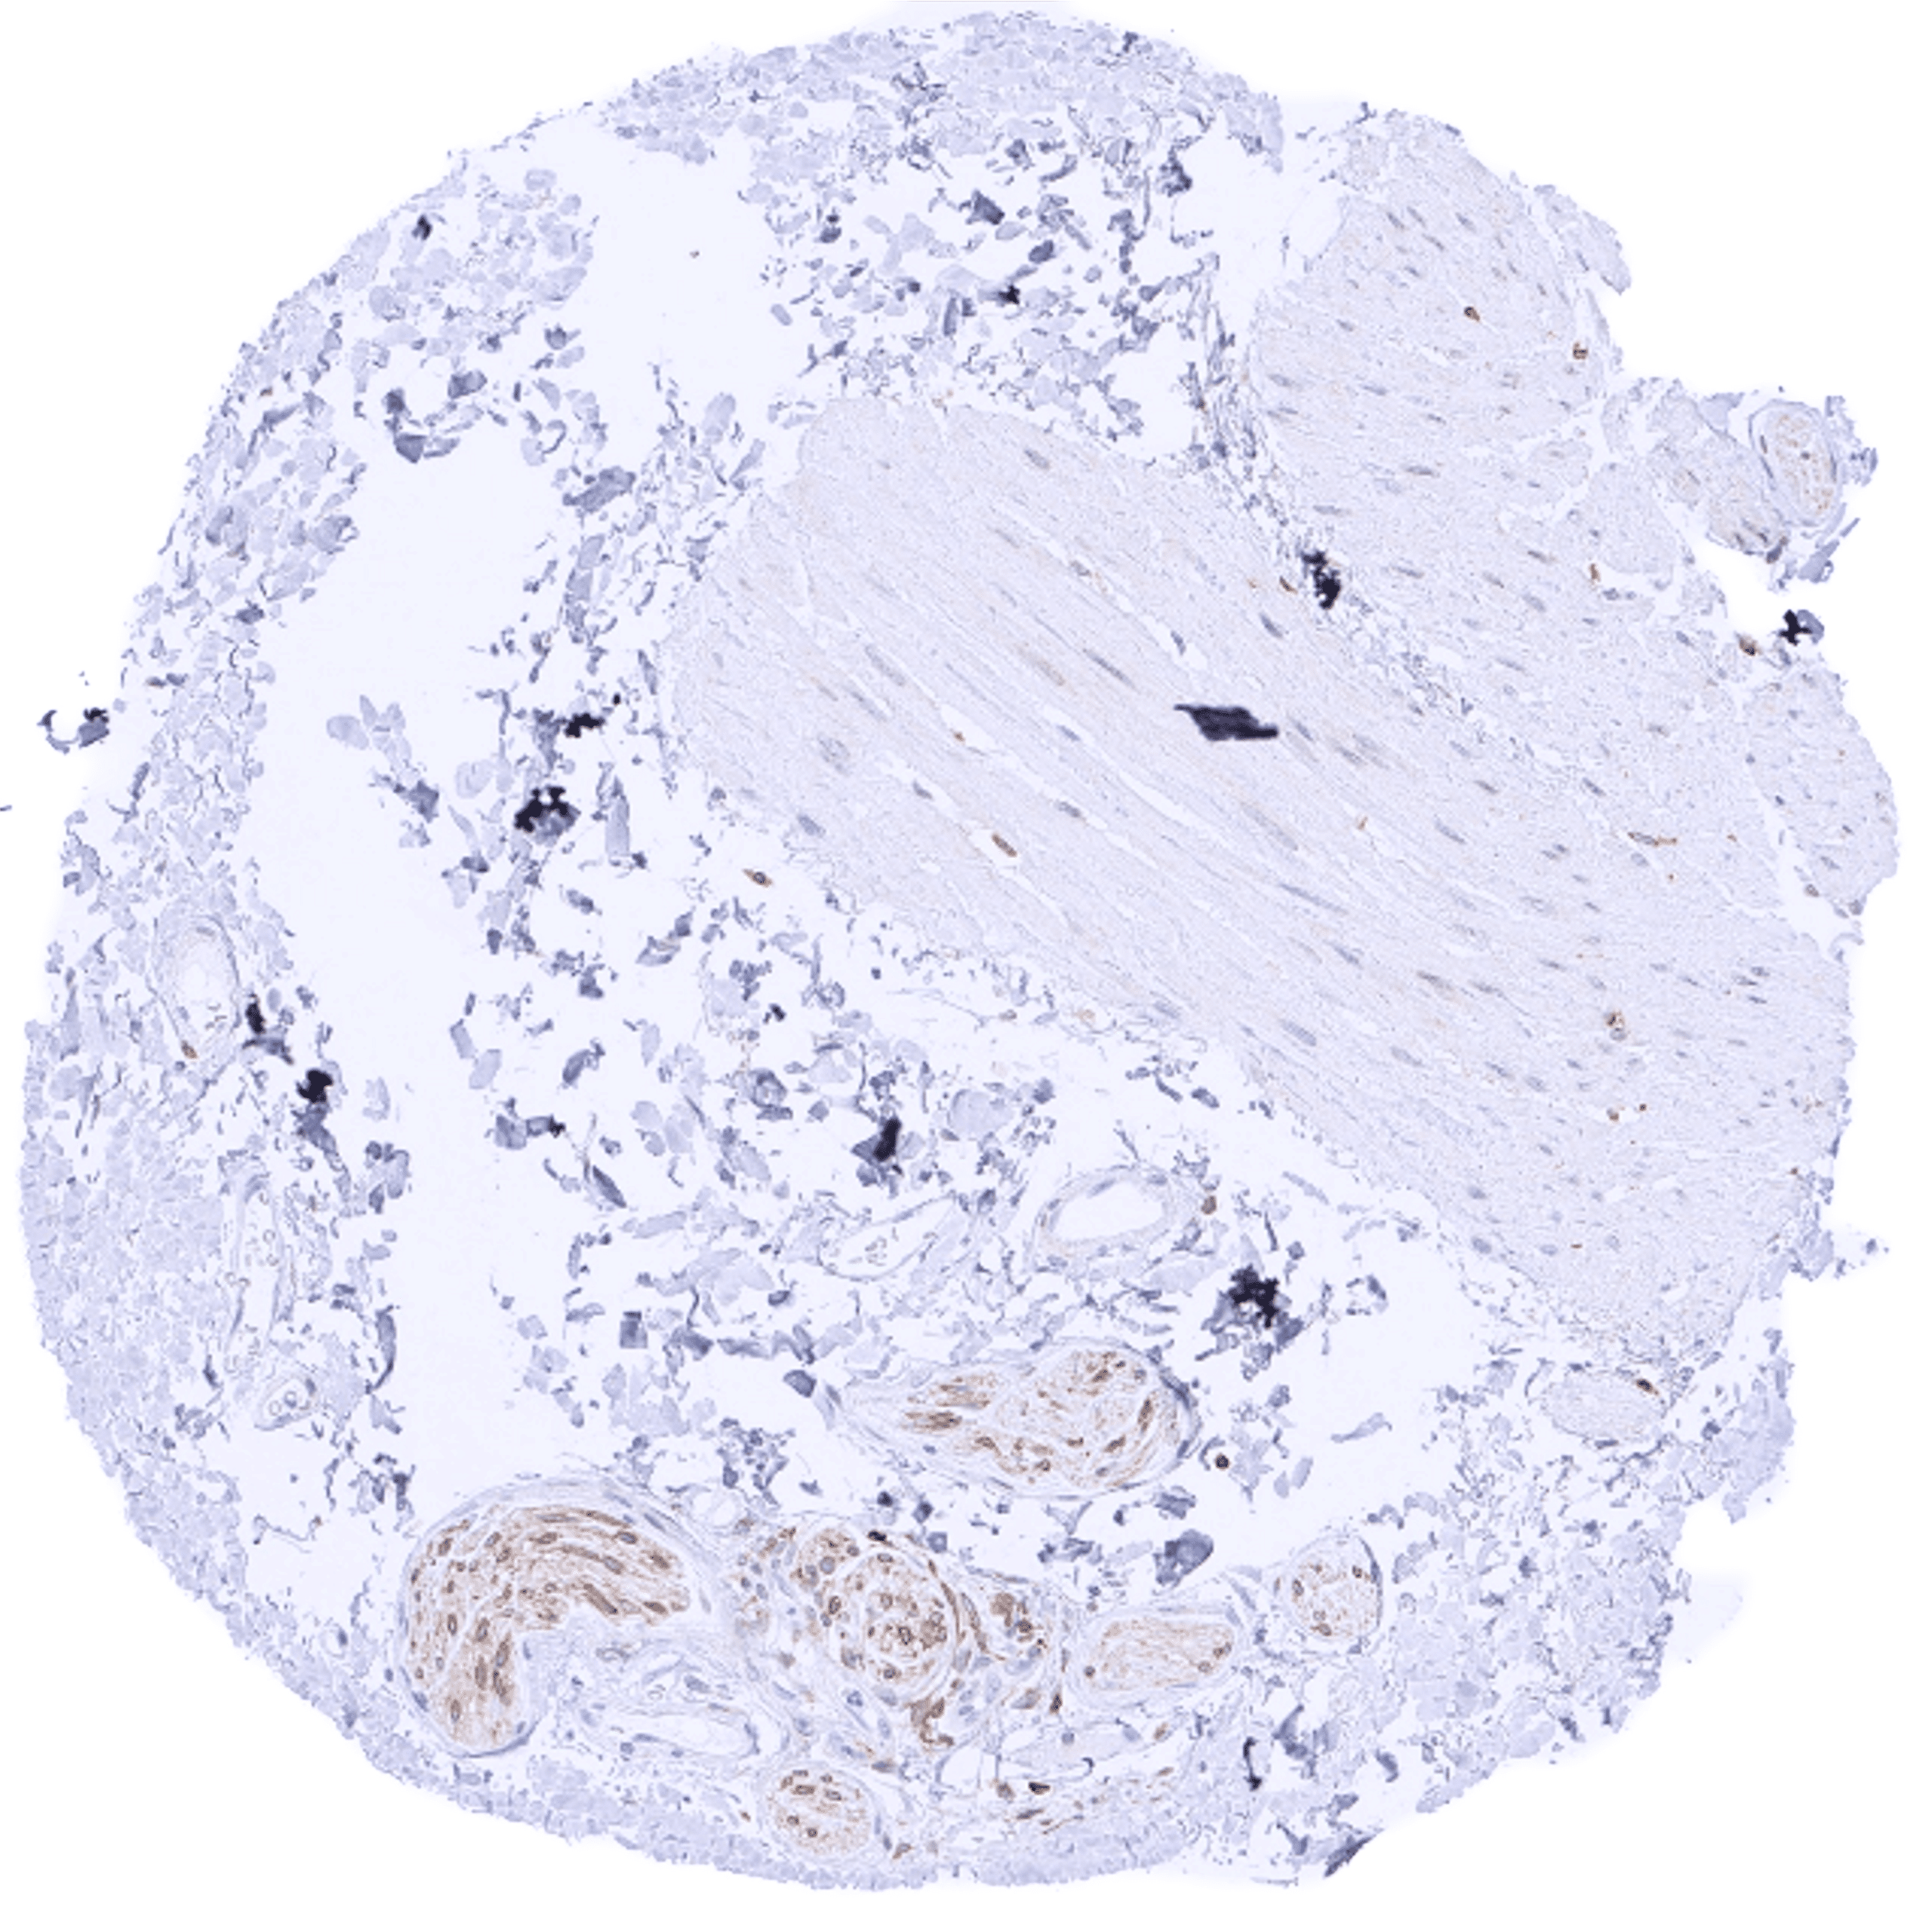

Comparison of antibodies: True expression of bcl-2 in all cell types with documented bcl-2 immunostaining by MSVA-402M is validated by identical staining patterns obtained by a second, independent commercially available bcl-2 antibody, termed “validation antibody” for all analyzed tissues.